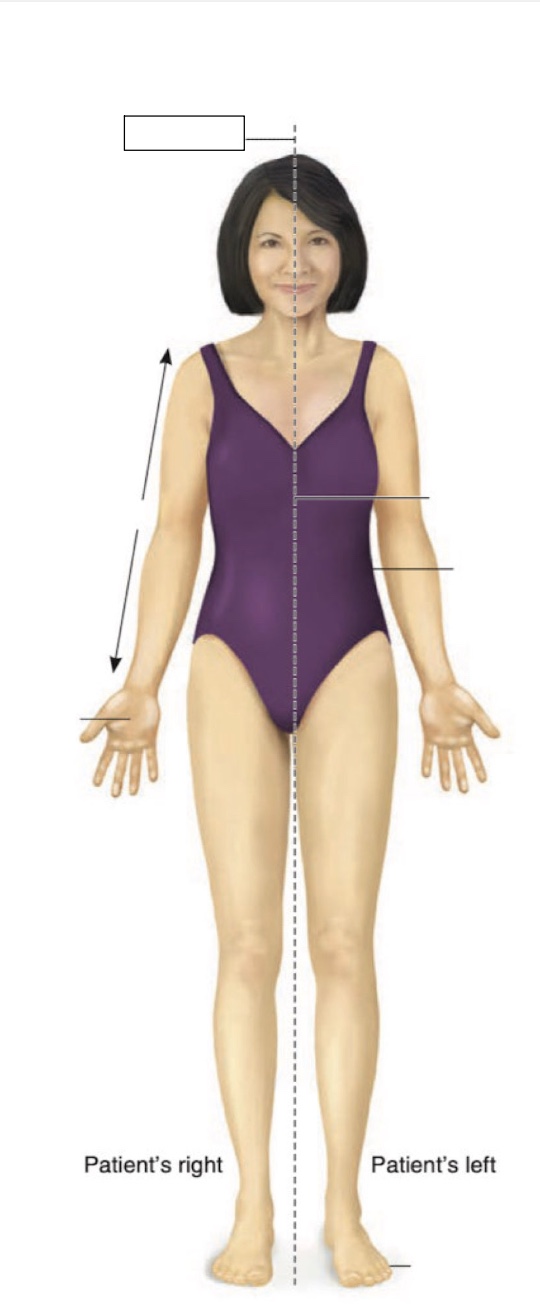

Anterior

Superior

Inferior

Midline

Medial

Lateral

Cranial region

thoracic region

umbilical region

inguinal region

genital region

femoral region

arm

forearm

cubital region